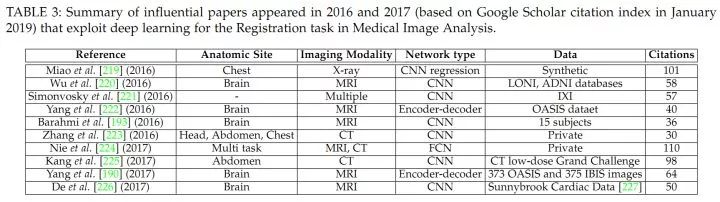

前人工作

1.经典方法

2.相关研究

医学图像配准(参考:Going Deep in Medical Image Analysis : Concepts, Methods, Challenges and Future Directions)